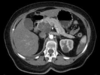

Ruptured AAA

AAA

Autosomal dominant polycystic kidney disease ## Footnote CT of the abdomen (coronal reformats) demonstrates both kidneys to be markedly enlarged by innumerable cysts ranging in size from a few millimetres to multiple centimetres. These cysts also vary in density: most are near-water density, some are hyperdense, others are calcified. Also present are numerous cysts in the liver. The pancreas is unremarkable. Features are consistent with autosomal dominant polycystic kidney disease, which was subsequently confirmed.

Sigmoid volvulus ## Footnote dilation causes the classic coffee-bean sign, a pathognomonic of sigmoid volvulus.